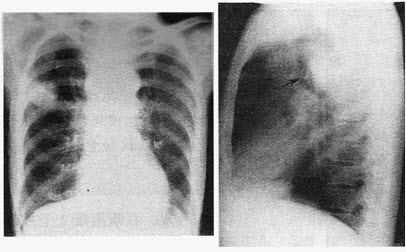

129������ѡ����

�����У�72�ꡣ�ΰ�����һ���࣬�ֳ���ͷ��ͷʹ��MRͼ�����£����п��ܵ�����ǣ���

A.��ת�ư�

B.��Ĥ��

C.�Խ�����

D.����

E.���ܰ���